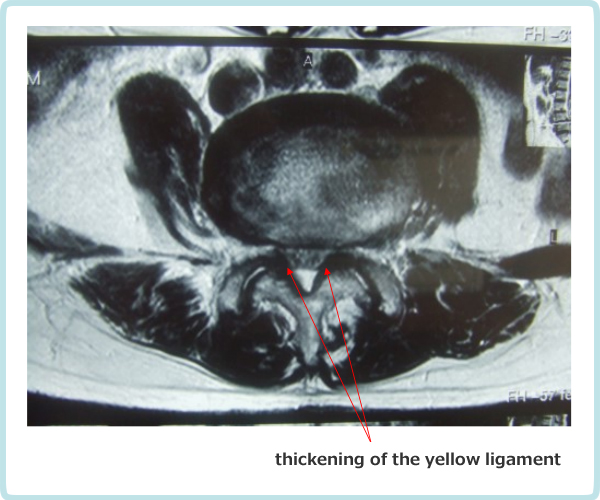

As shown in Fig. 2-1, the lumbar vertebrae have a vertebral foramen, which are connected vertically to form a canal called the spinal canal. The spinal cord is contained in this canal. The spinal cord is then surrounded by the following tissues. In front of the spinal cord, there is an intervertebral disc between the vertebrae, and behind the disc is a longitudinal ligament called the posterior longitudinal ligament. And behind the spinal cord, between the vertebral discs, is the yellow "yellow ligament". The spinal cord is surrounded by the vertebrae, intervertebral discs, posterior longitudinal ligament, and yellow ligament. When these protrude toward the center of the spinal canal due to deformation, herniation injury, or thickening, the spinal canal becomes narrower, putting pressure on the spinal cord causing spinal stenosis.

The mechanism of intermittent claudication is as follows. In scoliosis, the cauda equina nerve, which is located below the second lumbar vertebra. It resembles a horse's tail and is compressed by a deformed yellow ligament or vertebra causing pain and numbness in the lower extremities. The cauda equina nerve has longitudinally distributed blood vessels that supply oxygen and nutrients to the nerve root as shown in Figure 2-2.

As the lumen of the lumbar spinal canal narrows, the nutrient vessels of the caudal nerve are compressed and narrowed. When the lumbar spine kyphosis is strengthened by upper body loading (60% of body weight) during walking, the spinal canal is further narrowed and the pressure on the blood vessels becomes stronger. As a result, blood flow to the cauda equina nerve deteriorates, causing pain and numbness in the lower limbs, making walking difficult (intermittent claudication).

Figure 2-7. Compression of the cauda equina nerve from the dorsolateral aspect due to narrowing of the L3.4 intervertebral foramen and thickening of the yellow ligament